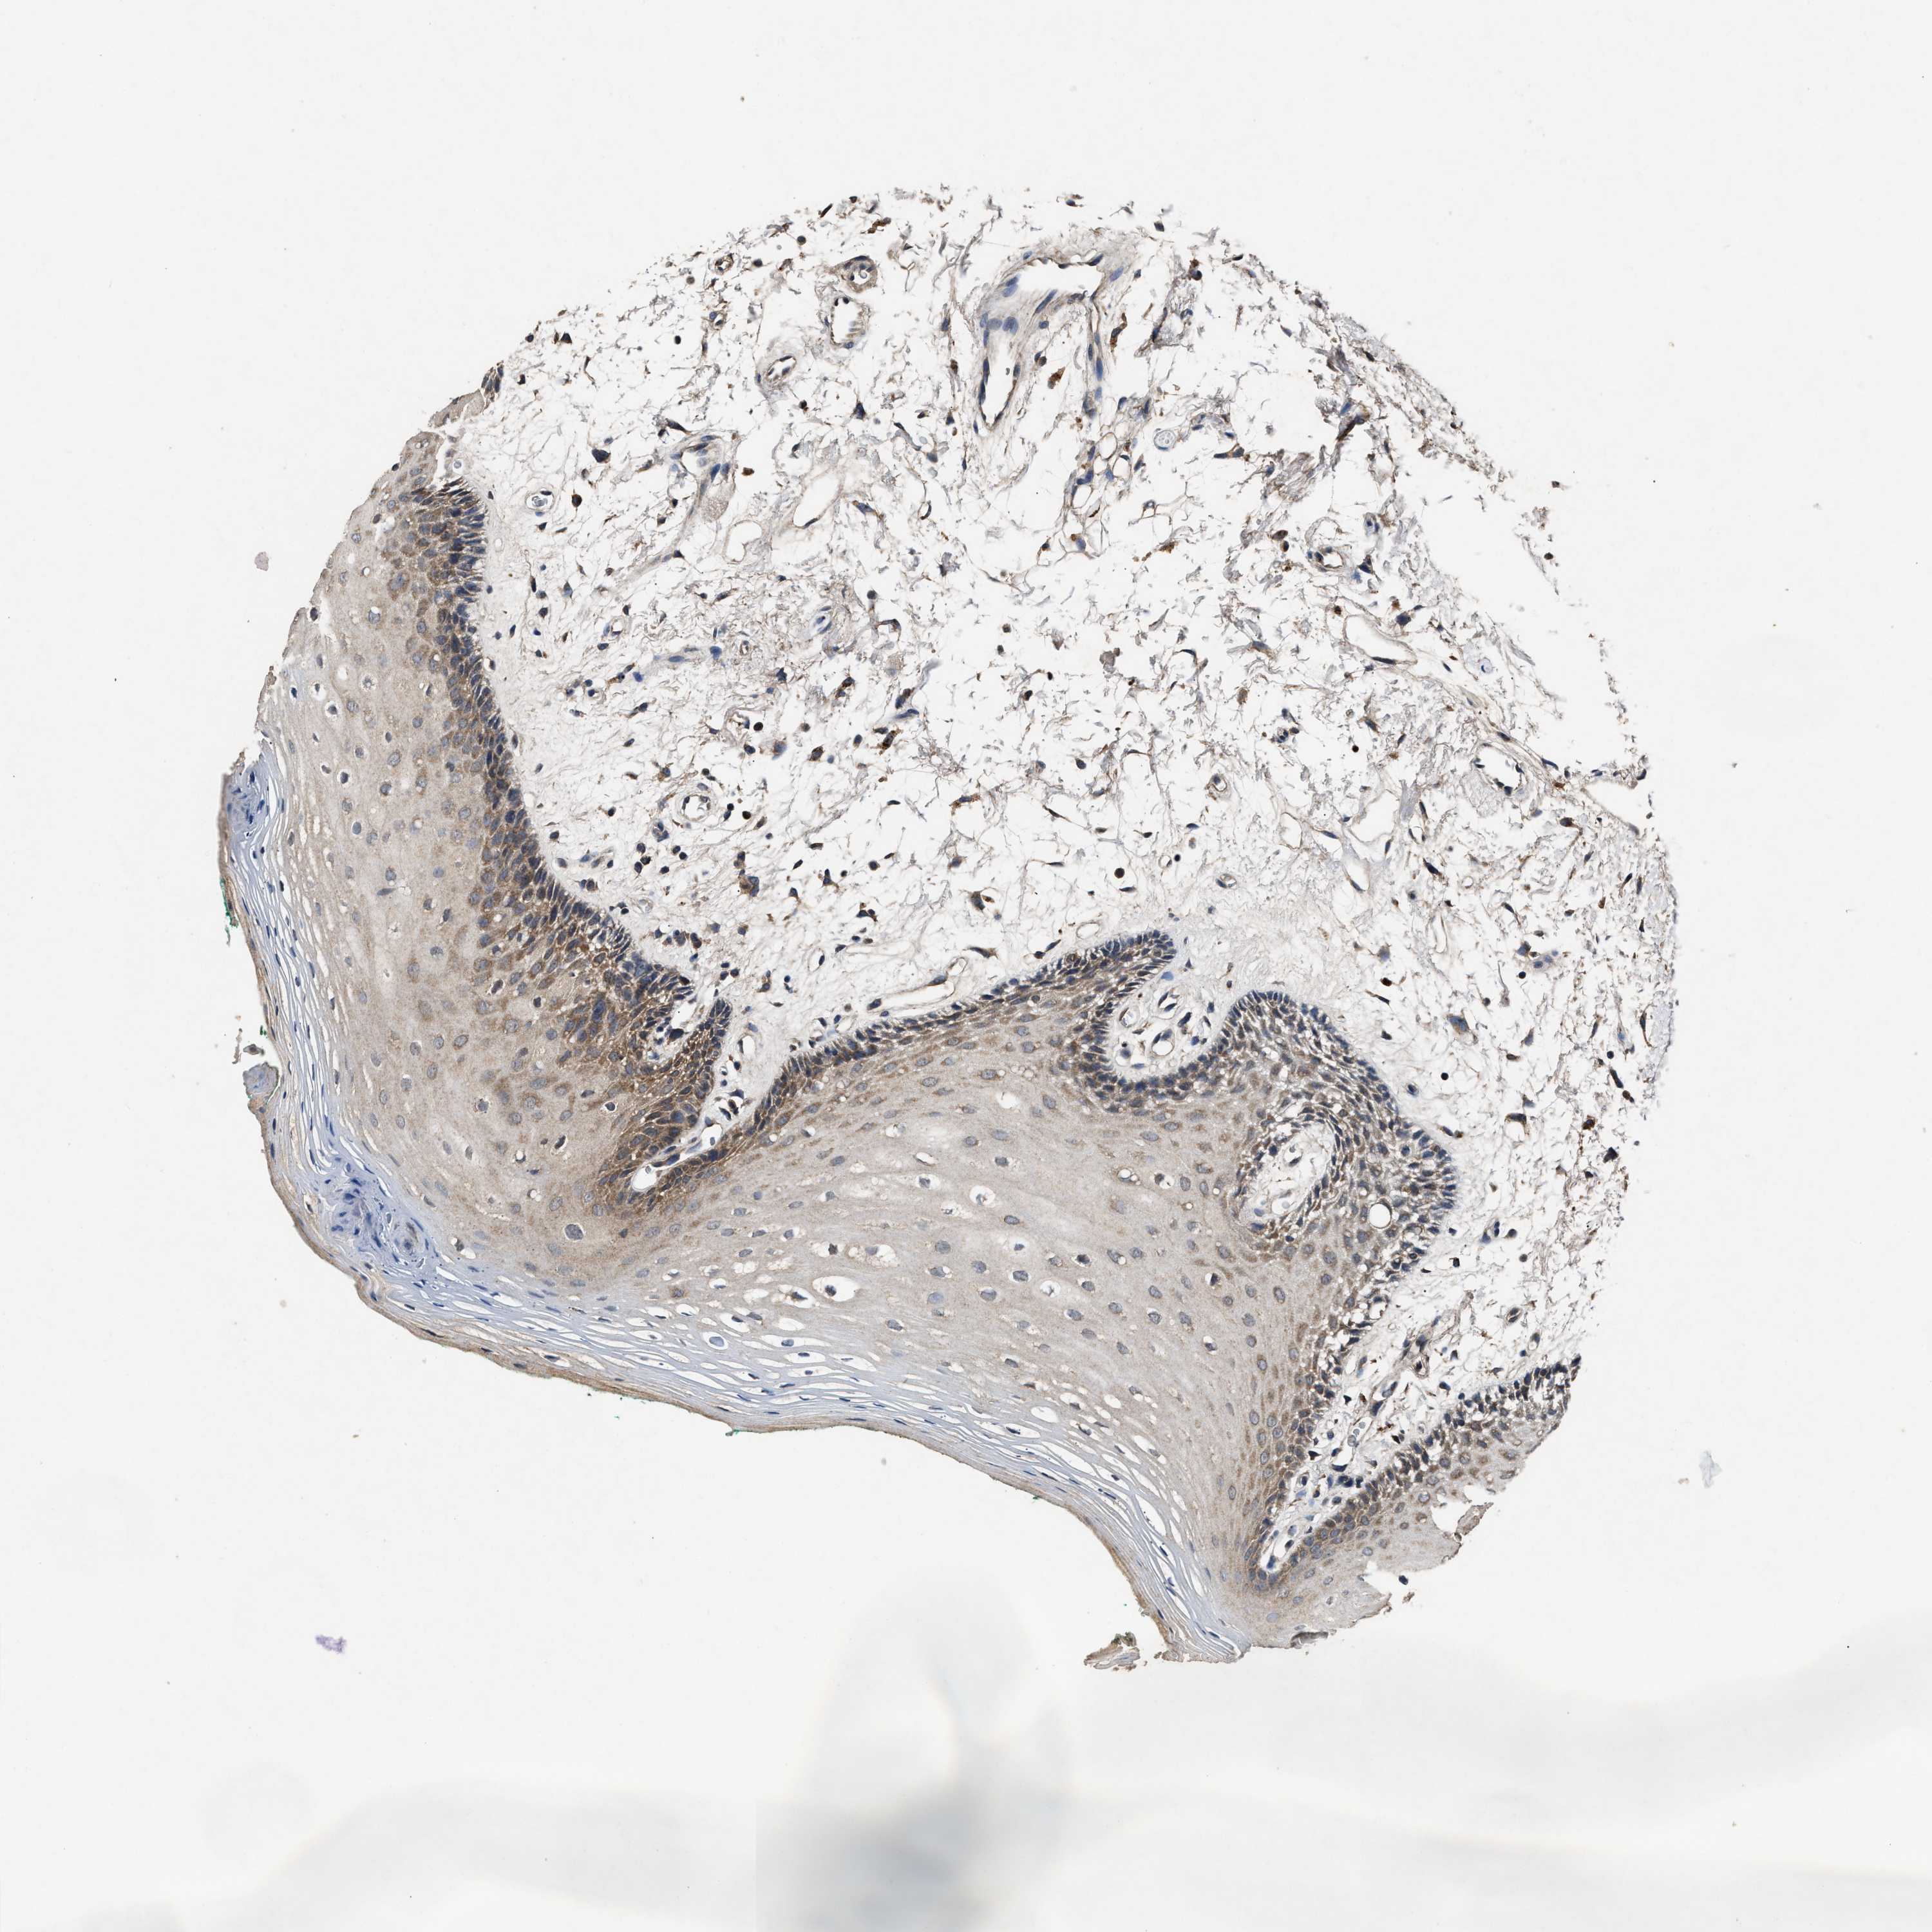

TISSUE PRIMARY DATA ORAL MUCOSA Show tissue menu

Oral mucosa

ORAL MUCOSA - Antibody stainingi

Antibody staining in the annotated cell types in the current human tissue is reported as not detected, low, medium, or high, based on conventional immunohistochemistry profiling in selected tissues. This score is based on the combination of the staining intensity and fraction of stained cells.

Each image is clickable and will lead to virtual microscopy that enables deeper exploration of all samples and also displays staining intensity scores, fraction scores and subcellular localization as well as patient and tissue information for each sample.

Antibody HPA050294Antibody HPA060836Antibody CAB021103

Squamous epithelial cells HighMediumMedium